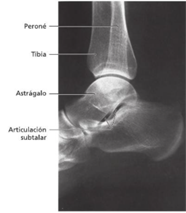

Está formado por cuatro huesos El peroné La tibia El astrágalo y el calcáneo |

Articulación subastragalina es la que se encuentra entre

La tibia y el peroné conforman una bóveda en la que encaja

la cúpula del tercio este permite movimiento de adelante y hacia atrás El astrágalo se apoya sobre el calcáneo formando una

articulación plana |

El tobillo esta

conformado por 3 huesos, estos son:

Tibia.

Peroné.

Astrágalo.

La articulación que

conforma esta estructura es:

Articulación

tibiotarsiana: Esta articulación está dada entre los maléolos de la tibia y

peroné con el tarso (astrágalo).